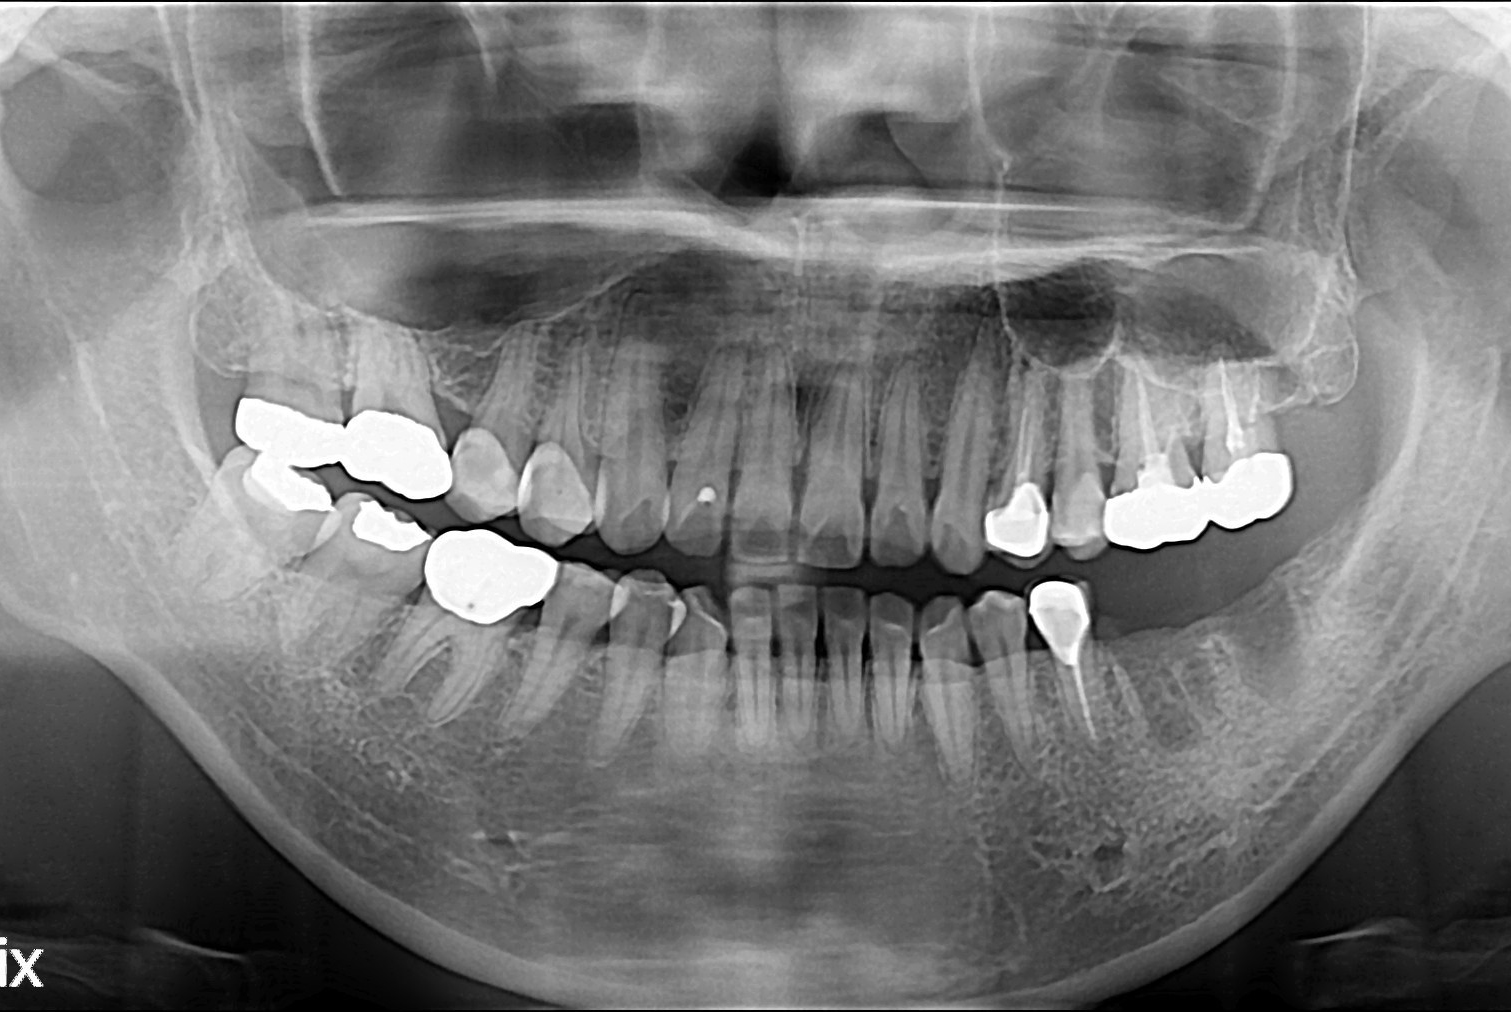

치료전 : 2017-01-21

정은이 후.jpg

치료후 : 2017-02-18

세종치과는 많은 환자와 다양한 케이스를 바탕으로 항상 편안한 임플란트 수술을 제공하고자 노력하고,

오래동안 튼튼히 쓸 수 있는 임플란트 수술을 가장 큰 목표로 삼고 있습니다